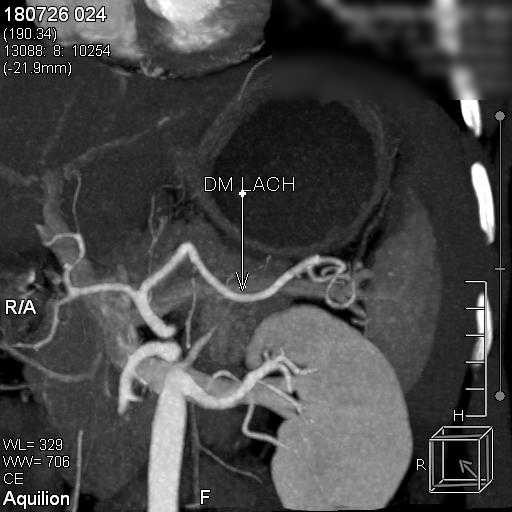

Suýt chết vì vỡ lách sau tai nạn giao thông dù không chảy máu ảnh 1hình ảnh động mạch lách của bệnh nhân

Bác sĩ CKII Nguyễn Phước Thuyết – Trưởng khoa Chẩn đoán hình ảnh, Bệnh viện Hoàn Mỹ Sài Gòn trực tiếp thực hiện, bằng cách luồn ống thông nhỏ từ động mạch đùi thông qua động mạch chậu vào động mạch chủ và đến động mạch lách.  Tại đây, Bác sĩ sẽ bơm thuốc cản quang nhằm xác định vị trí động mạch lách bị vỡ. Bác sĩ sẽ tiếp tục luồng một ống siêu nhỏ vào động mạch đang chảy máu và bơm keo vá chỗ thủng, giúp cầm máu và gắn liền nhu mô lách. Từ đó, truyền thuốc tắc mạch vào vị trí bị vỡ giúp tìnhtrạng chảy máu tại lá lách được kiểm soát.